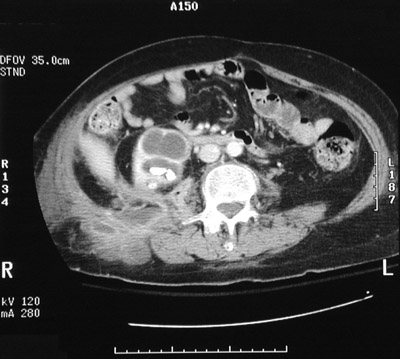

These abdominal CT scan views with contrast demonstrate a

staghorn calculus

filling a dilated calyx along with

marked hydronephrosis

as a consequence, extensive pyelonephritis resulted, and the infection produced an

abscess extending to the flank

.